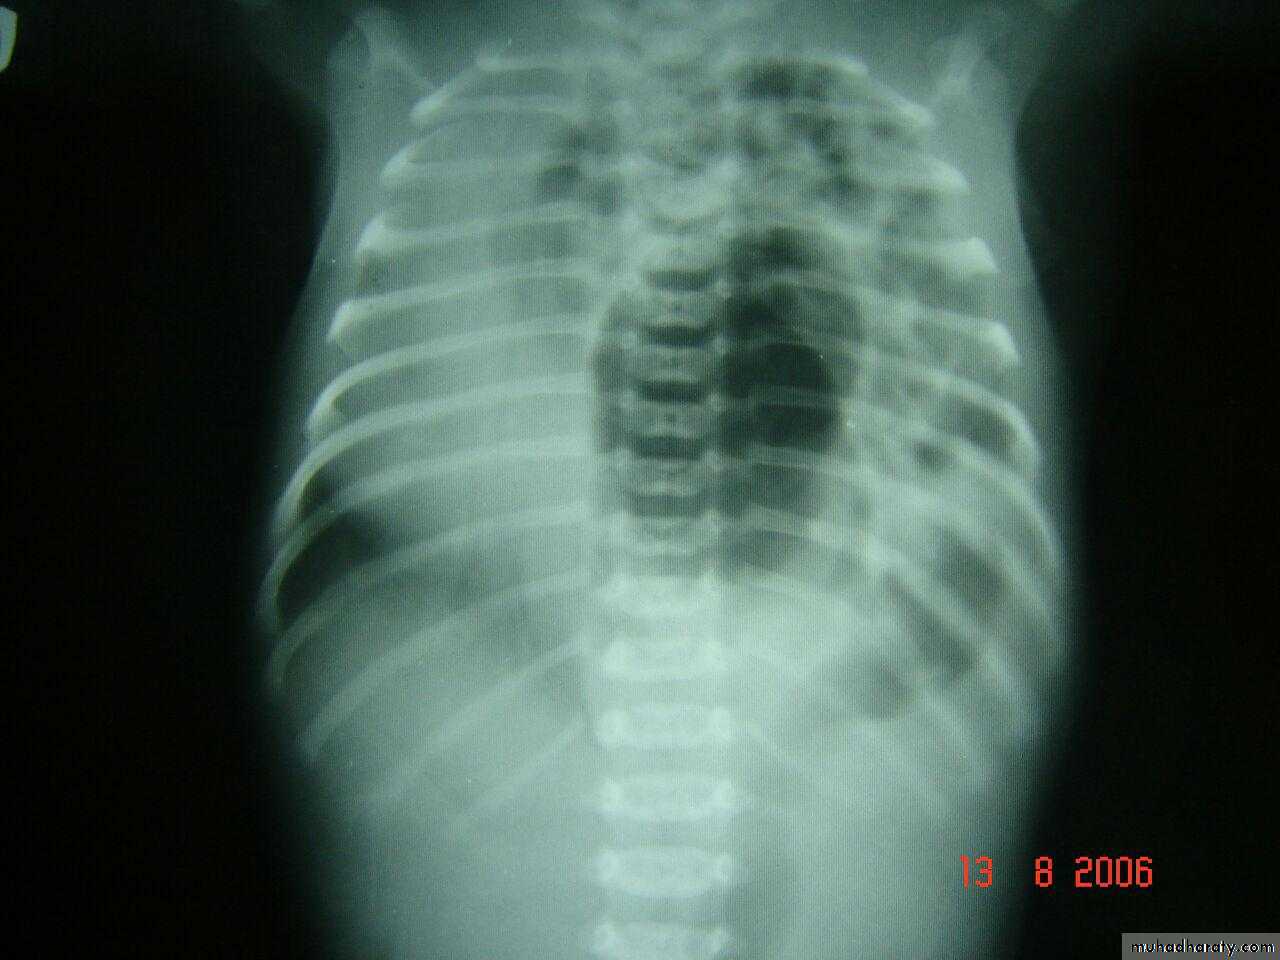

3 month infant presented with cough & dyspnea

Xray shows hyperinflated chest (depresed diaphragm , > 6 ribsMay be bronchiolitis

Hyperinflated chest

Hx of FB

A showing normal x rayB xray during expiration showing lt. lung emphysema make shifting of mediastinum